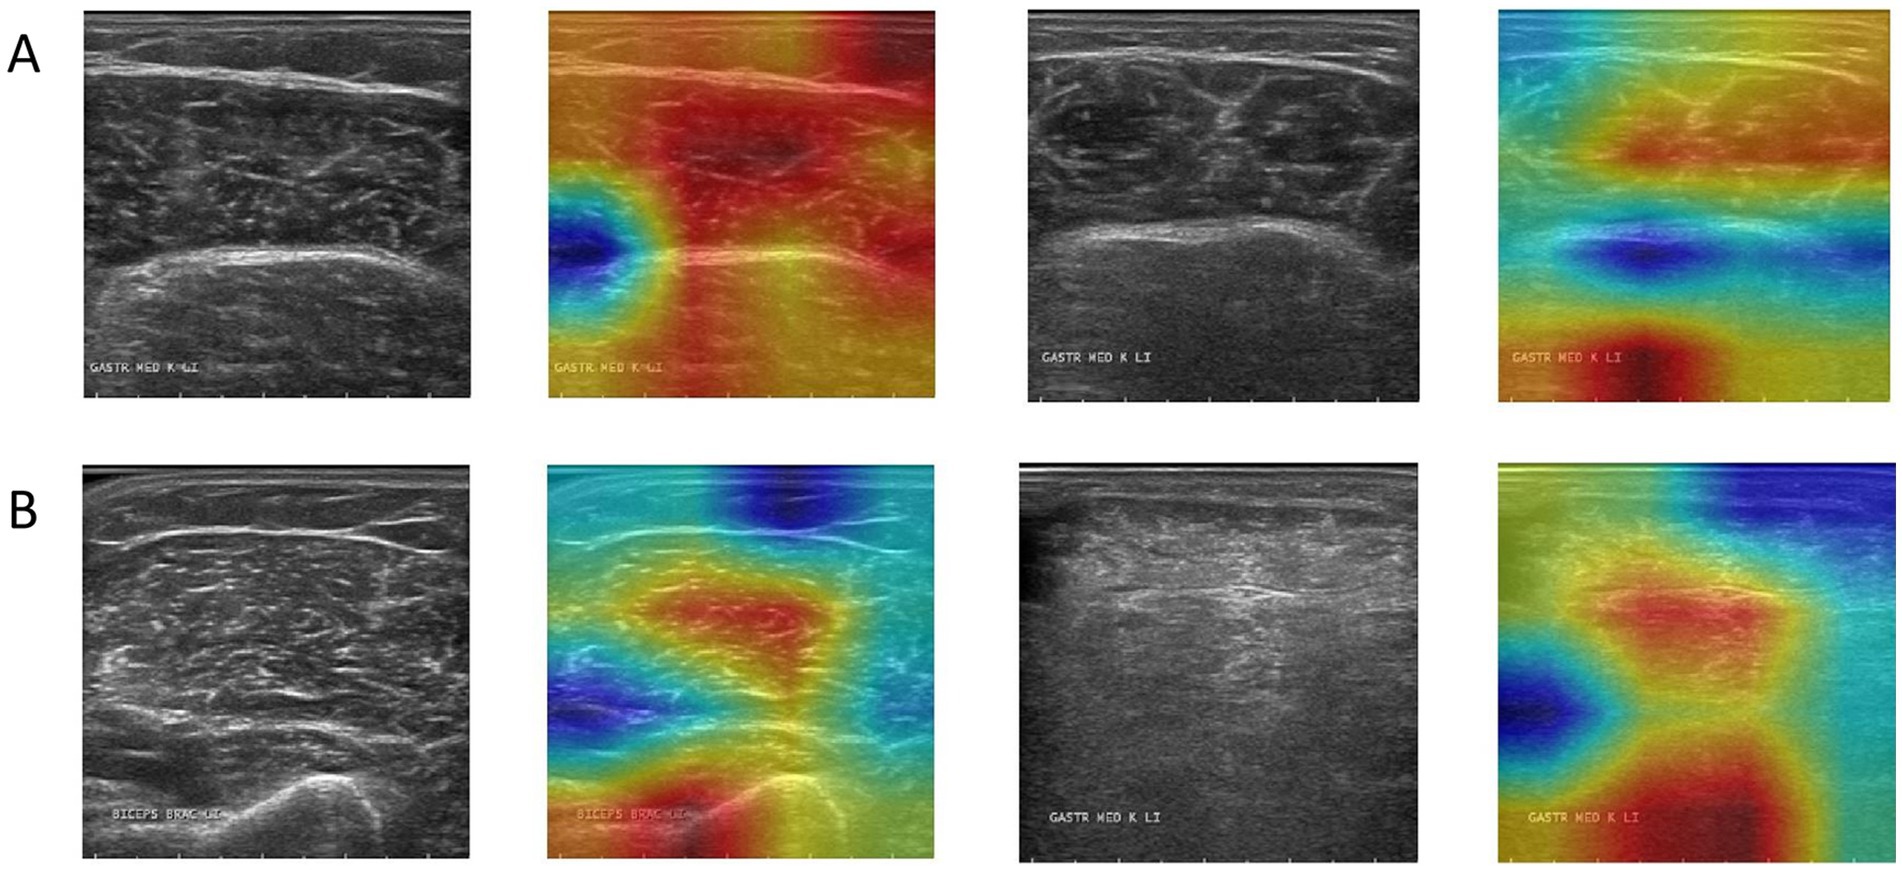

Grad-CAM was used to visualize the model’s focus areas on typical healthy and pathological muscle images (Figure 6). For healthy samples (Figure 6A), the high-response areas in the heat map concentrated on the transverse stripe-like texture corresponding to neatly arranged muscle fibers. For the pathological sample (Figure 6B), the high-response areas focused on regions with disordered echoes, blurred edges, or focal hypoechoic areas. These visualized regions correspond to locations of known pathological features.

Figure 6

Grad-CAM activation heatmap visualization, where (A) represents healthy samples and (B) represents abnormal samples.

We evaluated model performance using several quantitative metrics, including accuracy, precision, recall, F1-score, and the area under the curve (AUC). Accuracy measures the proportion of correct classifications and is the basic indicator for evaluating overall performance. Precision (also known as positive predictive value, PPV) is used to evaluate the proportion of the model’s predictions of the “pathology” category that are actually pathological, reflecting its ability to control false positives. Recall measures the model’s ability to identify pathological samples and reflects the risk of missed diagnosis. The F1-score, as the harmonic mean of precision and recall, is suitable for scenarios with uneven sample distribution. Finally, the AUC value reflects the stability and discrimination ability of the model at different decision thresholds and is an important basis for evaluating the generalization performance of the model (23). In addition to these quantitative metrics, we qualitatively assessed the model’s interpretability using Gradient-weighted Class Activation Mapping (Grad-CAM), a technique that generates a visual heatmap to identify the image regions most influential for the model’s classification decision. In these visualizations, the heatmap is used for a qualitative assessment of the model’s focus. Warmer colors (e.g., red) indicate regions that were more influential in the model’s classification decision, while cooler colors (e.g., blue) represent areas of lesser importance. This approach helps to interpret where the model is looking, rather than quantifying the precise importance of each pixel.

A critical analysis of the Grad-CAM visualizations, however, warrants a more nuanced discussion. As observed, the heatmaps occasionally highlight the boundary between the ROI and the masked background. This phenomenon can be attributed to the nature of Grad-CAM interacting with the pre-segmented dataset used in this study (24). The artificial, sharp edge resulting from the expert-provided segmentation masks creates a high-gradient region, which can become a prominent focus for the visualization technique (25). While this may suggest the model is learning from edge artifacts, it is crucial to interpret this alongside the model’s high accuracy. The strong performance indicates that the model successfully learns discriminative features from within the muscle tissue itself, as these are essential for distinguishing between healthy and pathological patterns. The boundary highlighting is more likely a byproduct of the visualization technique interacting with pre-processed data, rather than the sole basis for the model’s decision. This observation underscores a key challenge in applying post-hoc interpretability methods to pre-segmented images and reinforces the importance of our future research direction (26). Developing an end-to-end model that operates on unsegmented, raw ultrasound images would not only streamline the clinical workflow but also yield more authentic interpretability results, ensuring the model’s focus is entirely on natural anatomical and pathological features.